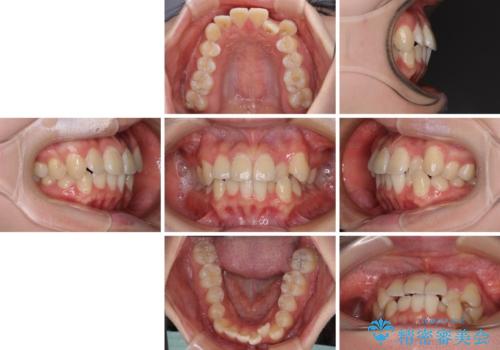

【モニター】八重歯と前歯のクロスバイト ワイヤーを併用しインビザラインで矯正治療

- 前歯のデコボコと八重歯を気にして来院された患者様です。

インビザラインでの治療を希望されていましたが、前歯のクロスバイトや下顎小臼歯の捻転が認められたため、インビザライン単独で治療を行うよりも、ワイヤー装置を併用した方が、治療期間の短縮やトラブル回避できると判断し、ワイヤー装置を併用することとしました。

まずはワイヤー装置により前歯のクロスバイトと下顎小臼歯の捻転を改善し、その後インビザラインにより全体を整える矯正治療を行うこととしました。